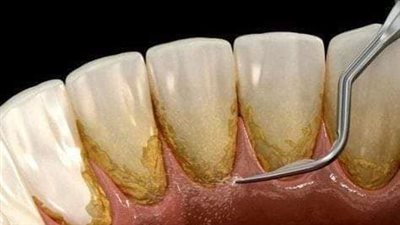

اعراض التهاب اللثة.. أهم أمراض الأسنان الصعبة